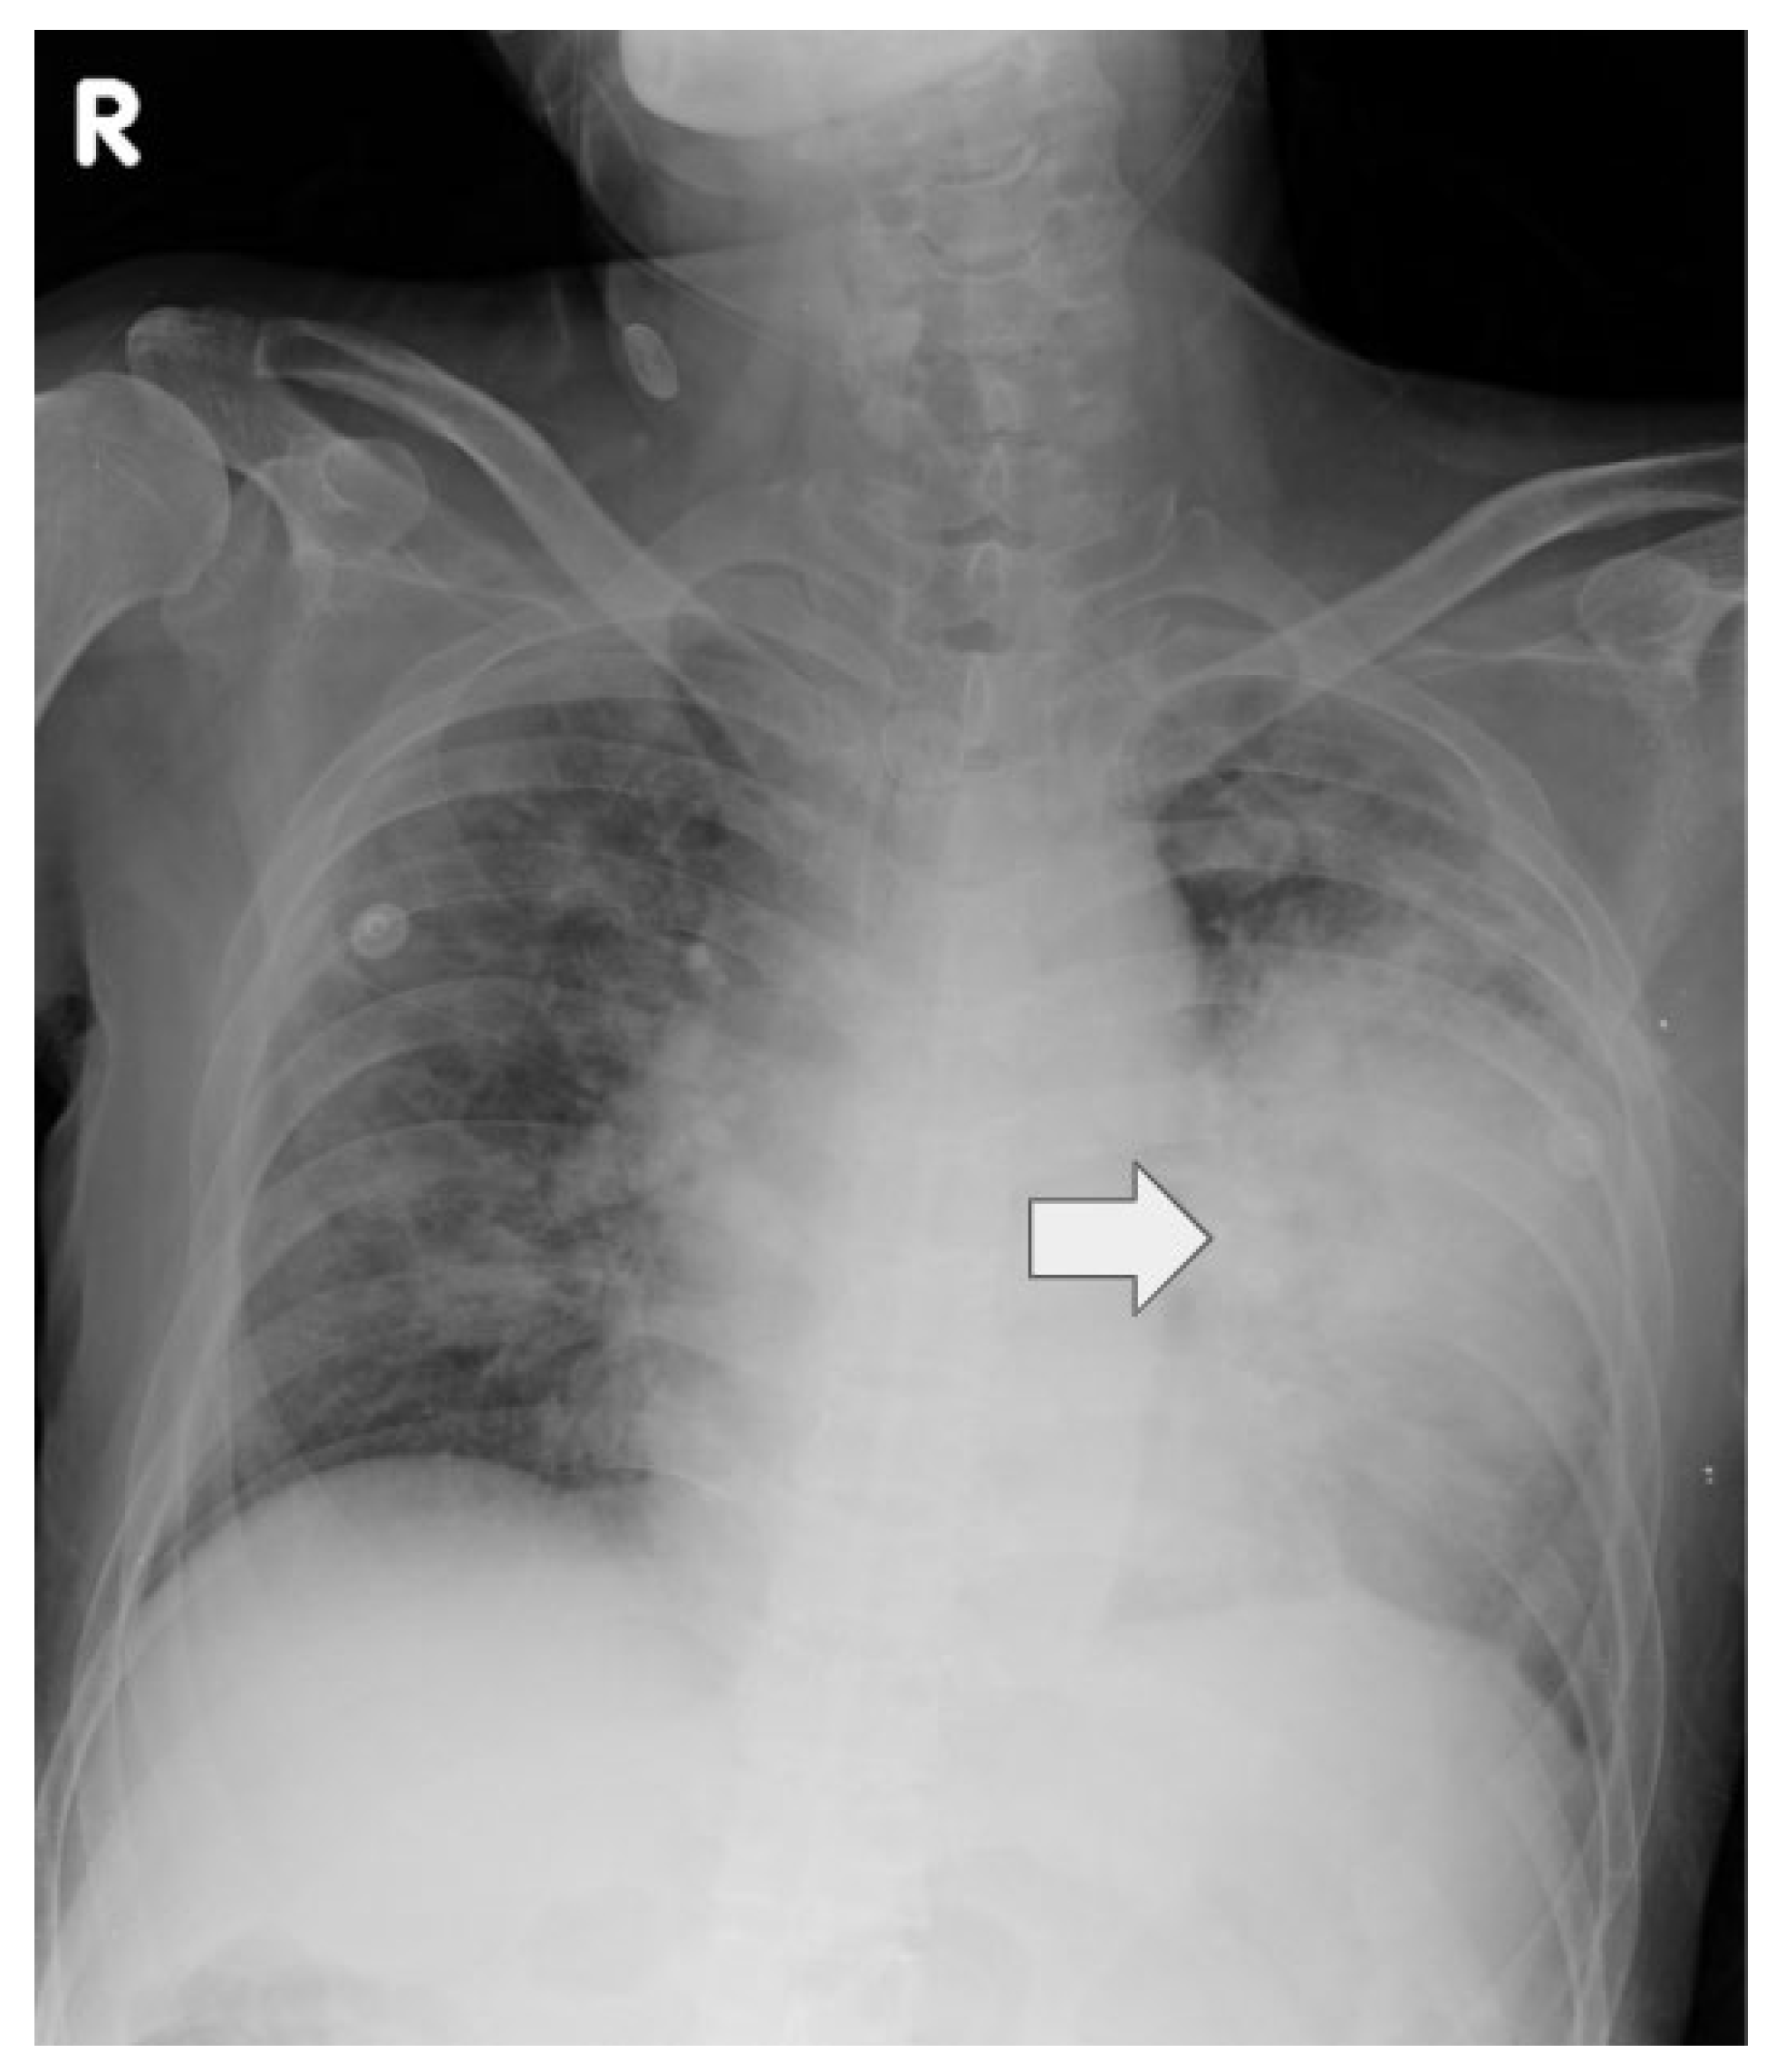

| 12/16 | Admission, intubation | CXR: bilateral pneumonia | — | Empiric abx, ICU admit |

| 12/18 | COVID PCR+, consult | CT: necrosis | Sputum: Nocardia cyriacigeorgica | Remdesivir, steroids |